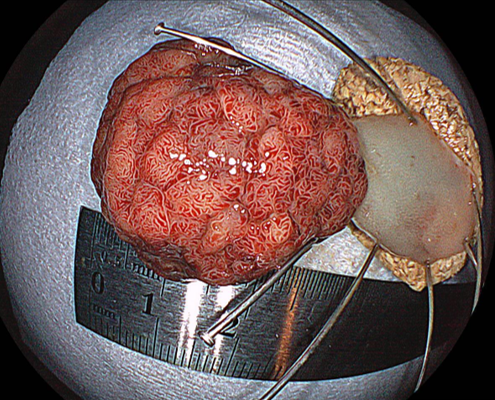

腫瘍径30×23×10mm 切除標本40×30×10mm

早期大腸癌(そうきだいちょうがん)

深達度(しんたつど):粘膜内(ねんまくない)

分化度(ぶんかど):中分化管状腺癌(ちゅうぶかかんじょうせんがん)

脈管侵襲(みゃっかんしんしゅう):陰性

治癒切除(治癒切除):取り切れて治っていること

Tis(M)N0M0 , Stage0でした。